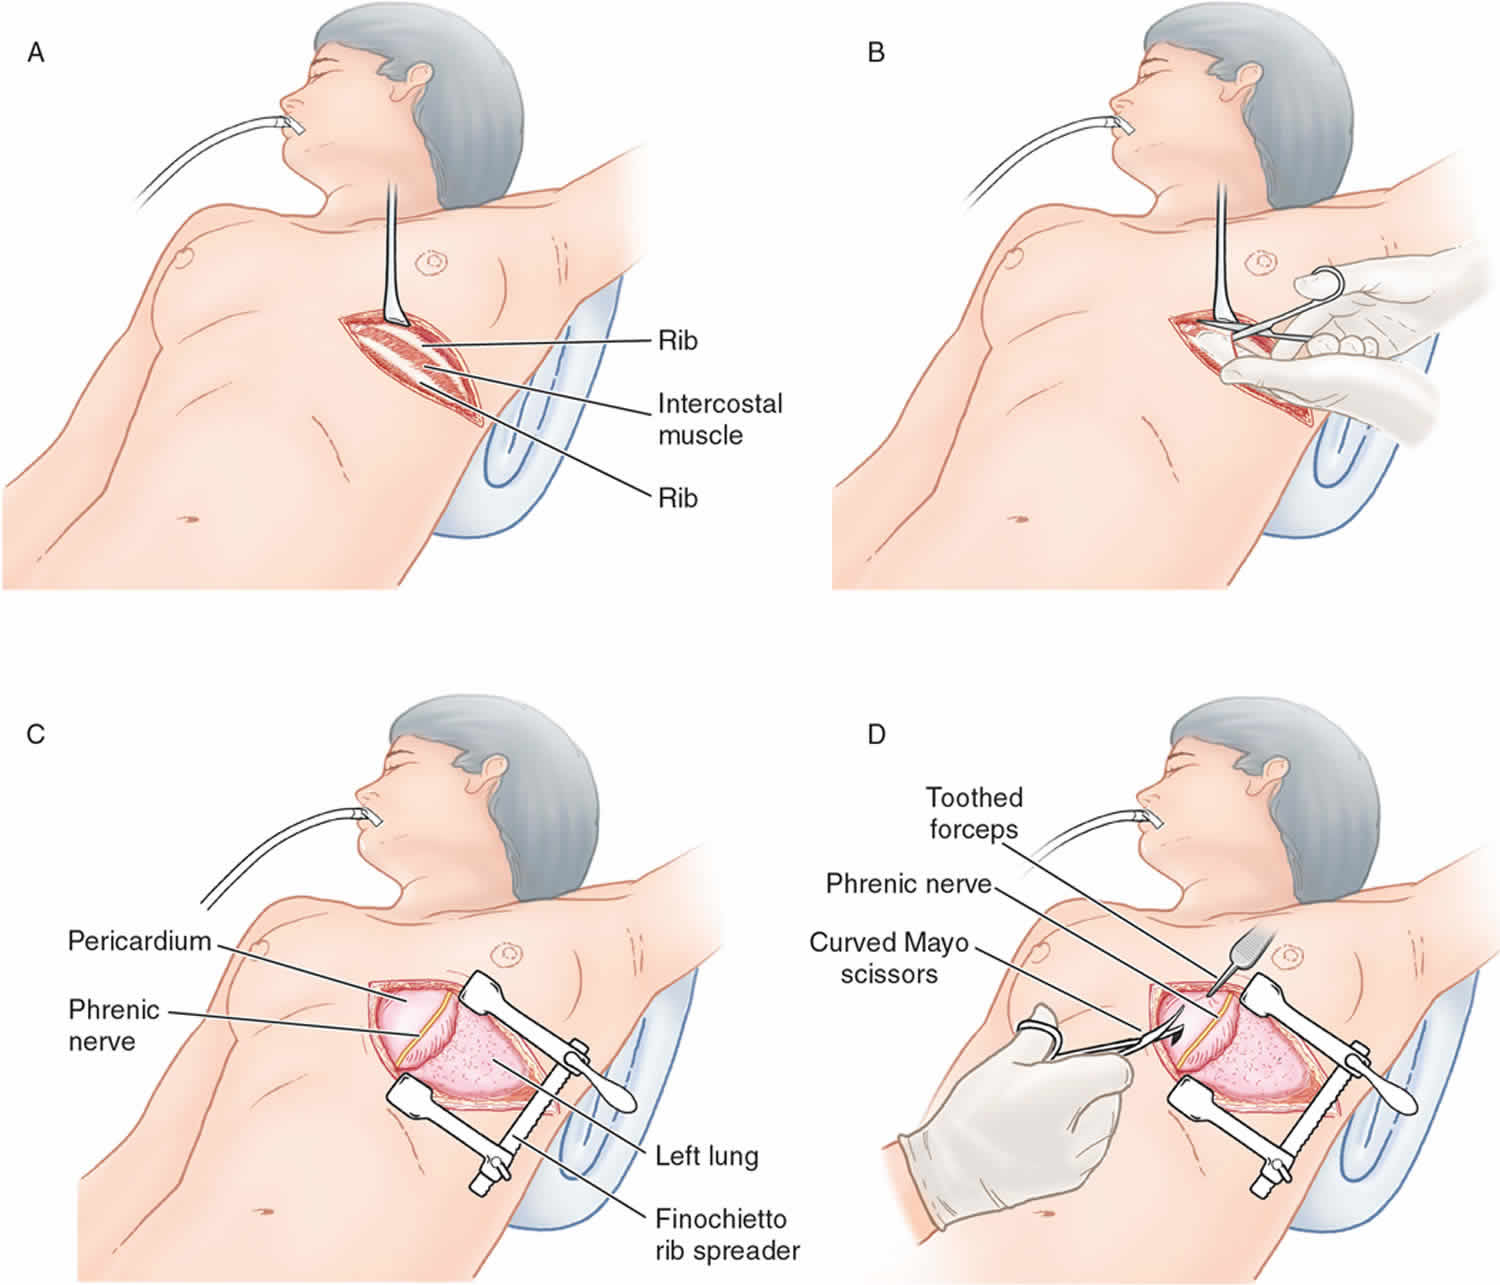

Clamshell thoracotomy is a large transverse incision that spans across the entire chest wall 1. It is also known as a bilateral thoracotomy and is used during massive chest trauma, lung transplant, or resection of tumors in the chest. The incision extends through the sternum, between the fourth and fifth ribs bilaterally, and extends to the mid-axillary line. Mammary vessels will be interrupted as well as intercostal muscles with associated intercostal nerves and vessels 2.

Figure 1. Clamshell thoracotomy

Control of the airway via standard orotracheal intubation technique is strongly advised prior to performing emergency thoracotomy. Selective intubation of the right mainstem bronchus is the preferred method. This allows for both ventilation and oxygenation of the patient via the right lung as well as decreased risk of injury to the left lung via decreased left lung expansion during a left-sided anterolateral thoracotomy. To intubate the right mainstem bronchus, directly visualize the vocal cords to pass the endotracheal (ET) tube into the trachea, and then blindly pass the ET tube to approximately 30 cm.

Use the left anterolateral thoracotomy approach when the site of the injury is unknown and the patient’s status requires immediate intervention for possible intrathoracic injuries.

Incision over the fifth rib with dissection into the fourth intercostal space provides the best access to the heart and great vessels. This incision is just beneath the nipple in men or along the inframammary fold in women.

The rib spreaders should be placed with the handle downward to permit for extension of the incision into the right chest if necessary.

Avoid making the incision too low. The location of the heart is commonly thought of as lower than it actually is.

The incision should be made just above the rib to avoid injury to the intercostals neurovascular bundle.

Use nontoothed forceps to lift the pericardium, and use small dressing scissors to open it in order to avoid ventricular laceration 16.

A simplified approach has been suggested in performing a “clamshell” thoracotomy to maximize exposure and minimize time of performance, requiring only a scalpel, nontoothed forceps, dressing scissors, and Plaster-of-Paris shears 31.